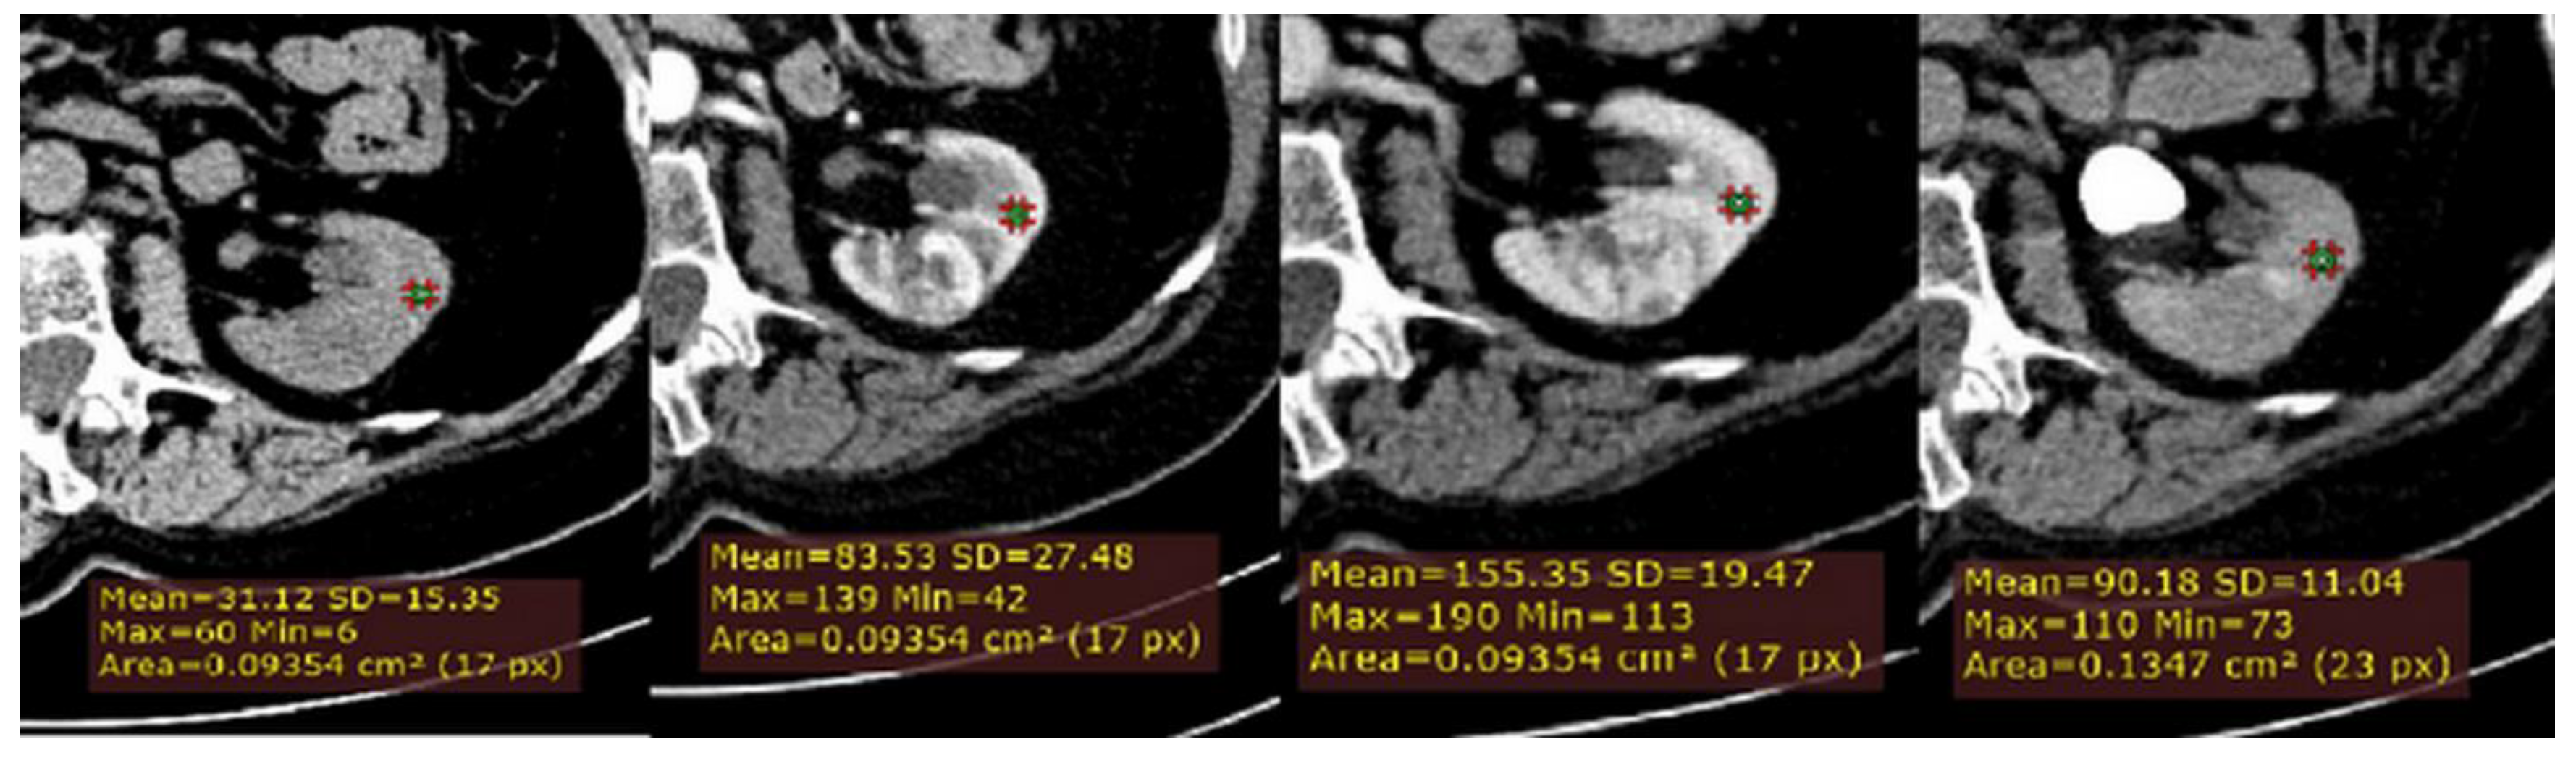

2.3. CT Image Analysis